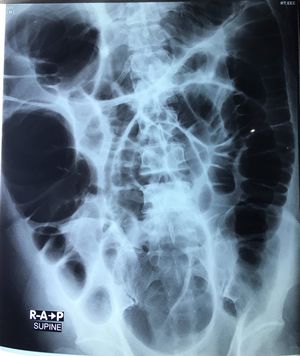

ICU patient 51/male Hypertensive. Poor compliance. Case of cvd bleed left putamen. Post pteronial craniectomy. Hospital acquired pneumonia. Physical exam: Protruberant abdomen yan. Hypoactive. Dull in percussion. Hypokalemic. On. Going correction With ngt.

Toxic megacolon, might be from pseudomembranous colitis secondary to pneumonia antibiotic treatment.